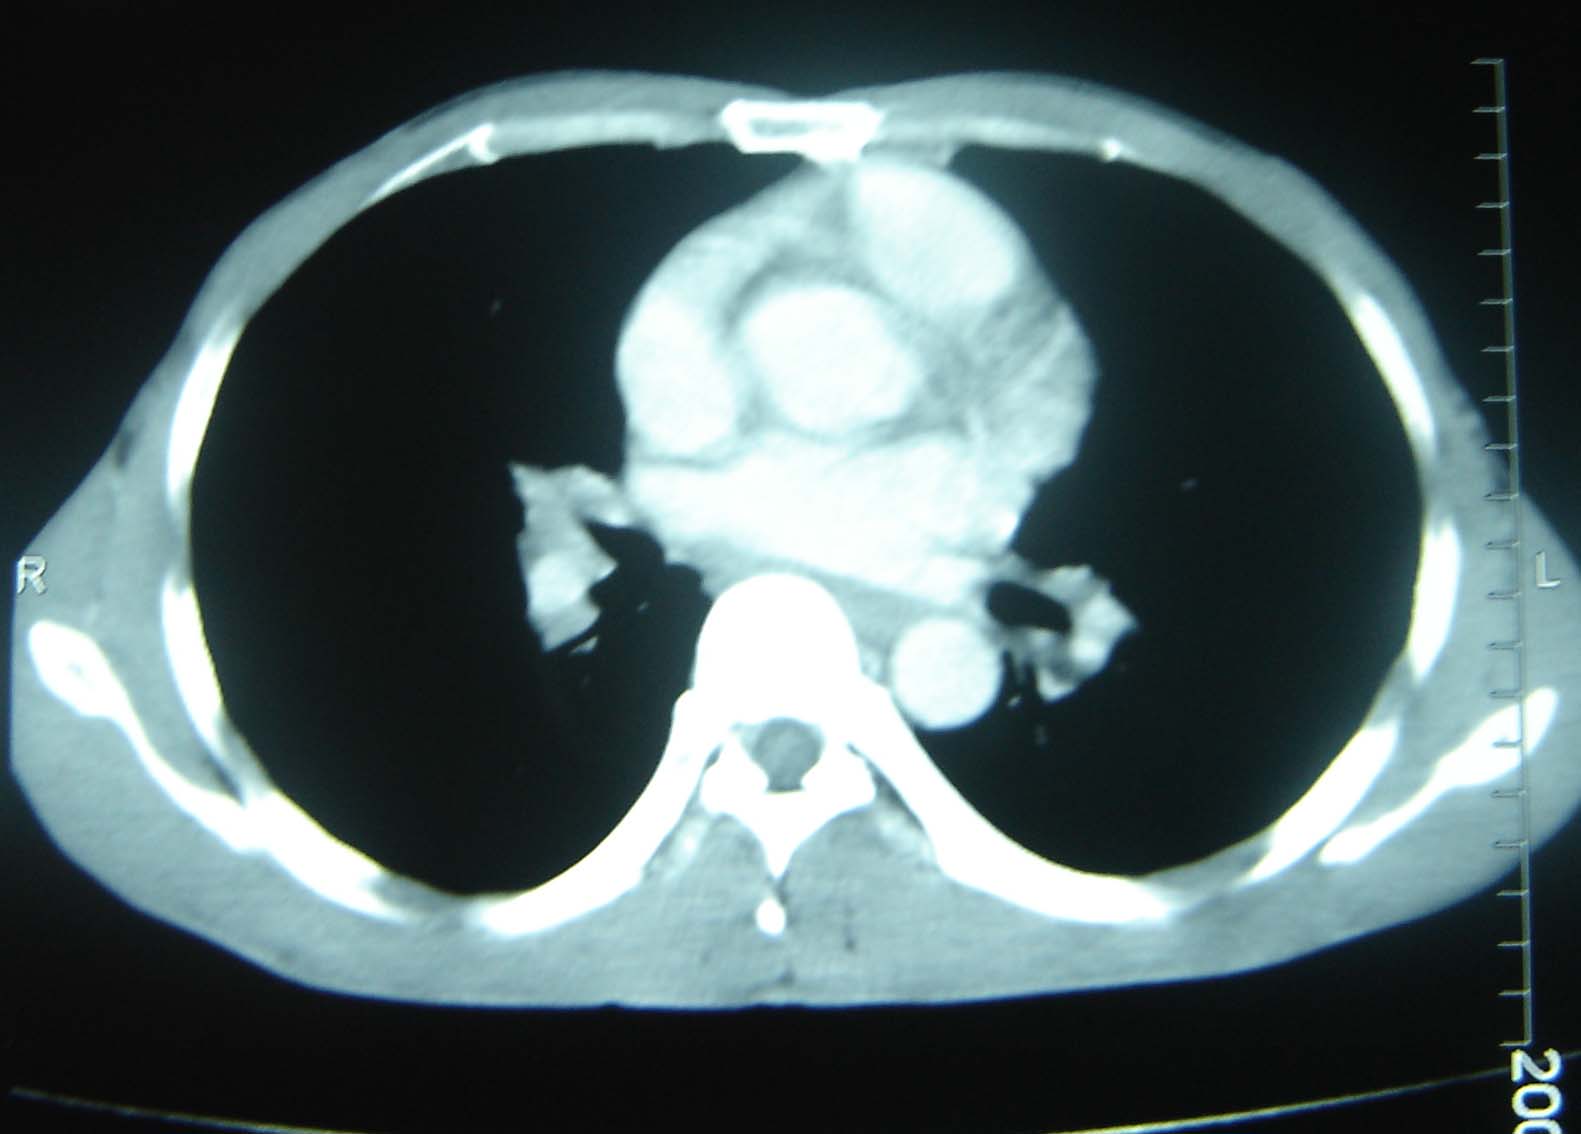

标题: CT25321:两肺多发结节 请会诊 [打印本页]

标题: CT25321:两肺多发结节 请会诊

男 、43岁,咳嗽胸痛,装修工,平时接触粉尘较多,有吸烟史10多年,纤维支气管镜检查未发现异常,胃镜、腹部b超检查亦未发现异常,颈部淋巴结活检未发现肿瘤细胞。

不能排除转移,如果不能找到原发灶,只有短期随访。

结节病?转移瘤?

1)考虑双肺及胸膜多发性转移瘤。2)肺气肿。